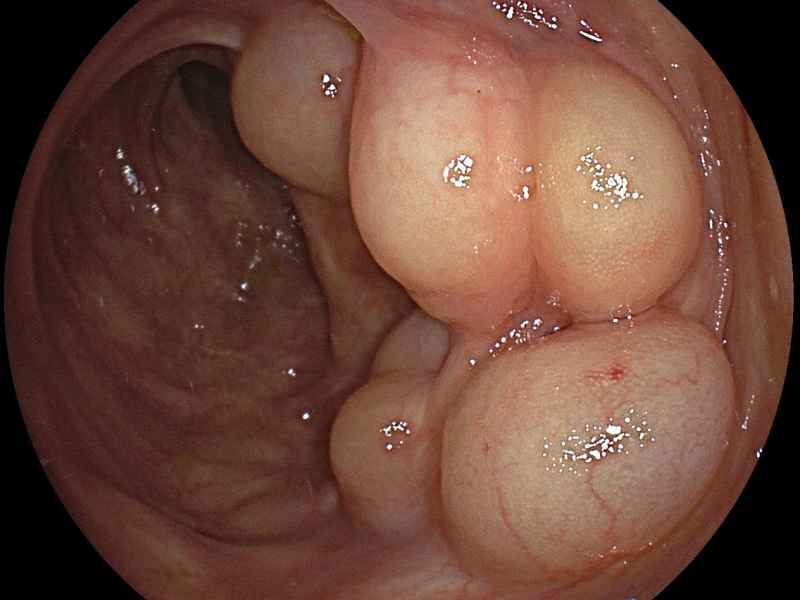

Idiopathic chronic pneumatosis intestinalis: a rare incidental endoscopic finding